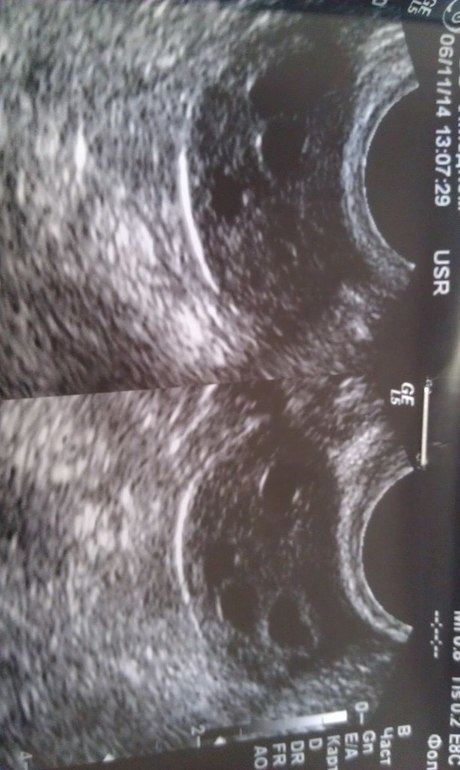

я что то может не понимаю.....тут же много фоликулов и нет доминантного, не правда?

нет. Доминантный будет на ПЯ как сказала врач. В тот цикл был в левом. Меняются. Фолликулов не много (4-5 шт) нет мелкокистозной структуры и фолликулярный аппарат ярко выражен.

у меня так же было на узи как то , мне сказали мультифоликулярные Я....еще на узи если пойдете, скиньте фото плиз, у меня тоже спкя((((

если не выбивается ни один в доминантные, то да,ставят мультифолликулярные. но МФЯ и СПКЯ вещи разные все таки. Вот мое узи с СПКЯ. Множество фолликулов, более 8 в срезе и все мелкие